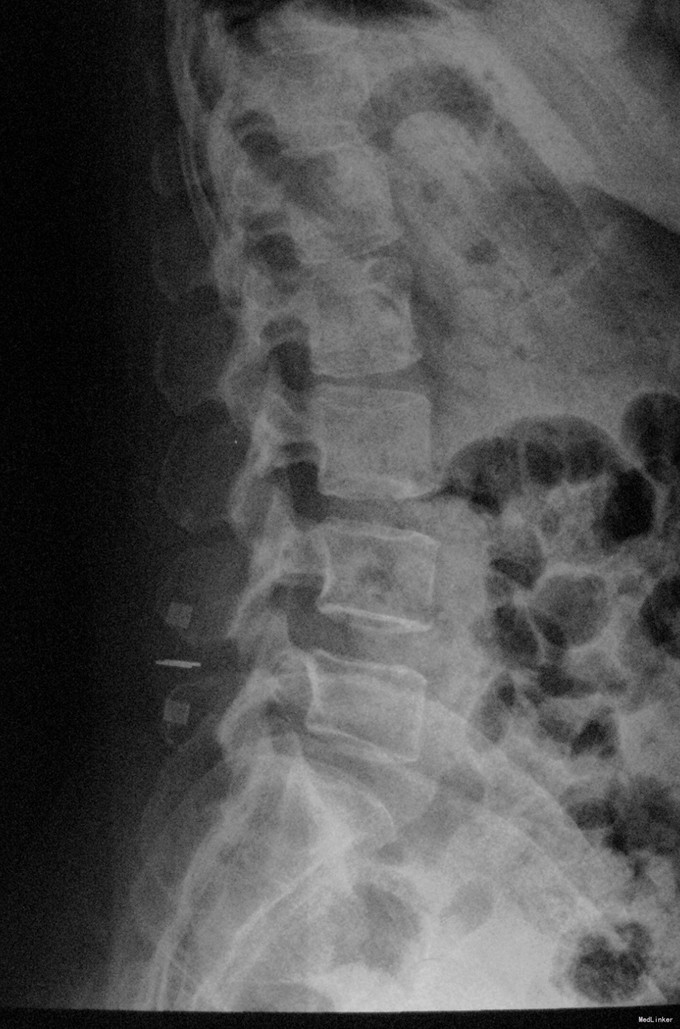

查体:脊柱生理弯曲存在,腰椎活动受限,L4/L5棘突压痛叩痛,叩击痛。双侧直腿抬高试验(-)。双下肢皮肤感觉正常,双侧髂腰肌、股四头肌、双侧胫前肌、踇背伸肌肌力Ⅳ级,腹壁反射、肛门反射正常,两侧膝正常,双侧踝反射未引出。双侧Babinski征(-),双侧皮温及色泽正常,双侧足背动脉搏动良好。 辅助检查:X光片示:动力位片显示腰椎4/5椎间失稳。MRI检查显示:腰4/5椎间盘突出,黄韧带肥厚致椎管狭窄,相应节段硬膜囊受压改变。

诊断:腰4/5椎管狭窄并失稳症。 治疗:给予行后路腰4/5右侧椎板间开窗减压椎间盘摘除并肥厚黄韧带切除+棘突间wallis固定术。